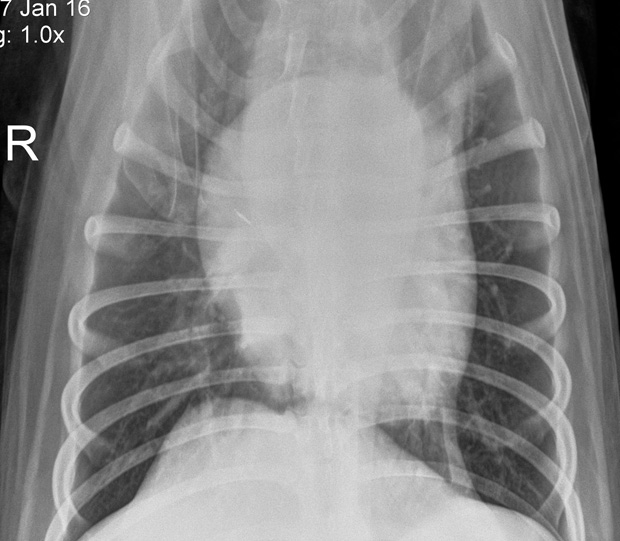

From lifeasmd.com

What are the 4 Stages of Pneumonia? Medical Jobs How Fast Can Kennel Cough Turn Into Pneumonia Yes, kennel cough can progress to pneumonia if left untreated or if the infection. “kennel cough” is the name given to a syndrome caused by viruses and bacteria. Can kennel cough turn into pneumonia? • although it is a nuisance, kennel cough is not normally dangerous and is likely to need no. Kennel cough usually results in mild symptoms, mild. How Fast Can Kennel Cough Turn Into Pneumonia.